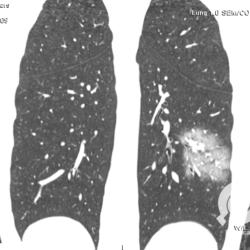

Os agentes etiológicos infecciosos são variados (bactérias, vírus, fungos, parasitas…), mas o que ocorre nos pulmões durante uma infecção por qualquer tipo de agente é a substituição do ar alveolar por secreção (pus, muco, eventualmente sangue ou necrose…) e com isso a manifestação radiográfica vai ser a mesma já que todas estas secreções apresentam a mesma densidade radiográfica: partes moles.

E o nome dado a esta alteração radiográfica que corresponde à substituição do ar alveolar por líquido é a consolidação alveolar.

Uma consolidação alveolar é, por definição, uma opacidade (imagem densa, branquinha) homogênea ou às vezes heterogênea (pela presença de calcificações ou cavidades), de limites mal definidos, exceto quando toca a pleura da parede ou das cissuras pulmonares. É um termo usado tanto em radiografia, como em tomografia computadorizada. Na tomografia, um outro termo é usado: vidro fosco, que é uma opacidade (branquinha mas não tanto como a consolidação), que borra o pulmão mas deixa ver os vasos de permeio (igual bigode de adolescente: dá pra ver todo o fundo).

Nós vamos mostrar aqui um pequeno apanhado de pneumonias de variados agentes, em diversos segmentos e lobos pulmonares, com extensões variadas. O objetivo é identificar o padrão radiológico de consolidação alveolar e não determinar o agente infeccioso, isso vai ser assunto para mais adiante. Aliás já antecipo que é fundamental saber localizar a lesão, porque alguns destes bichos gostam de determinados segmentos, alguns tumores também têm as suas preferências, então localização é fundamental. Se localização não fosse importante, um apartamento na beira do mar sairia o mesmo preço de um apartamento de frente pra BR-101, concordam?